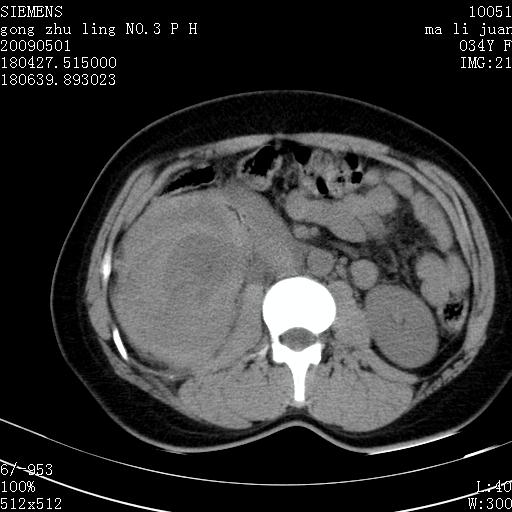

标题: CT19733:右肾碎裂

青年女性,骑摩托车摔伤。

右肾碎裂伤,包膜下血肿。

术中仅见右肾碎裂,肾蒂血管未见断裂。